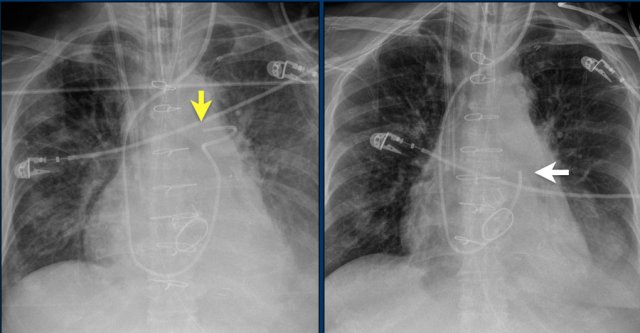

Here a patient with a normally placed ICD on the left image.

Months later there was malfunction due to ICD box and lead rotation (yellow arrow) and retraction (white arrow).

Here another patient with the Twiddler's syndrome.

Notice curling of the lead near the pacemaker and at the tip in the right ventricle (arrows).